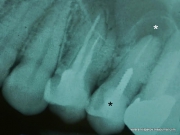

Открываю новую рубрику - "Вскрытие показало", где мы будем рассматривать удаленные зубы и находить всевозможные интересности. Я это делал спорадически, и формат мне настолько понравился, что стоит того, чтоб превратить это в постоянную рубрику. Сегодняшний случай - малый коренной зуб, кот ...